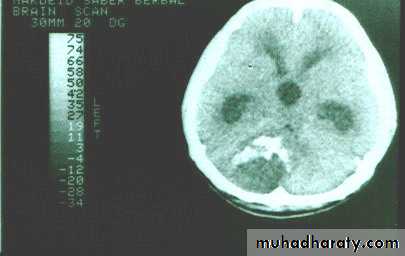

Meningioma

Benign tumor arise from the arachnid cells of the meningeal covering of the brain are most common primary intracranial neoplasm

Usually present in middle age female

it is well defined extra axial , located mainly at the convexity of the skull periphery

rounded or sessile , plaque like , specially the tumor arise from the cribriform plate , or those arise from the petrus bone , planum spheniodale , or from skeleton of the pituitary fosse .

CT finding

meningioma presented as isodense area or slightly hyper density area with surrounded crescent of hypo density ( csf cap ) post contrast injection the lesion enhance homogeneously with enhancing Dural tail .

20 % show calcification

hyperostosis & thickening of the near by bony part of the skull & diplioc space .

it may be associated with little or no peri focal edema .

if the lesion associated with central necrosis with large perifocal edema meningio sarcoma should be excluded .